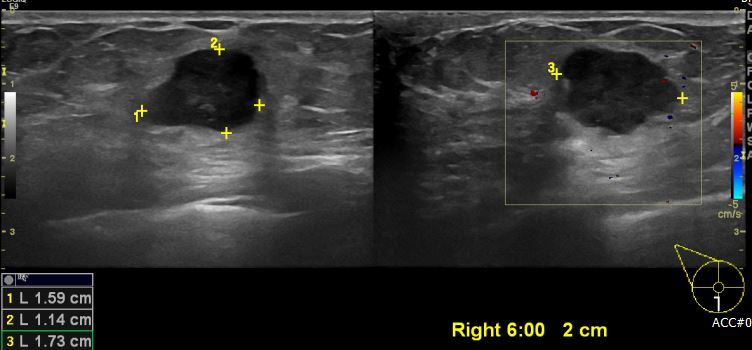

상기환자 우측 만져지는 멍울로 내원하신 70대 여성분으로 본원 초음파 시행 후 우측 6시 방향에서 2cm 떨어진 거리에 의심 스러운 혹 조직검사 시행하여 우측 침윤성 유관암 진단 되었습니다.